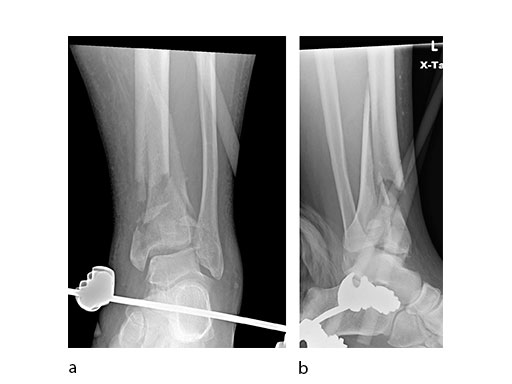

A 17-year-old male patient was involved in a snowboarding accident. This was a closed injury, and he was initially splinted for 10 days. His injury pattern demonstrated anterior articular impaction (Fig 1).

Surgeons performed an anterolateral surgical approach and distracted the joint using the distraction clamp and osteotome (Fig 2). The fracture was fixated with a VA-LCP Anterolateral Distal Tibia Plate (Fig 35).